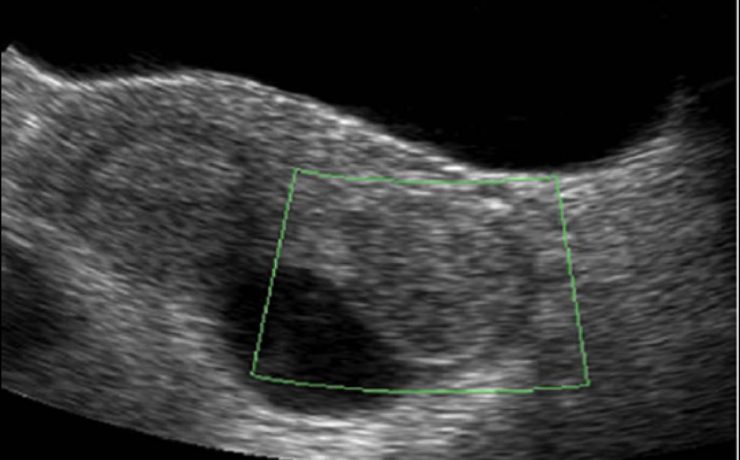

El cólico nefrítico se define como un dolor agudo en el flanco (en ocasiones se irradia a la ingle) escrito por los pacientes como el peor de su vida y que generalmente se acompaña de náuseas, vómitos y hematuria. La litiasis es un agregado policristalino compuesto de cristaloides (95%) y